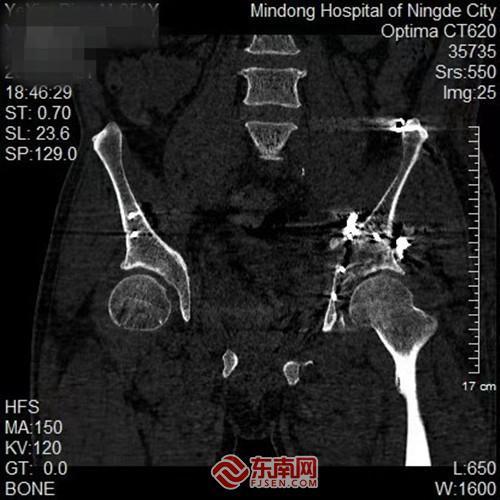

术后影像。闽东医院供图

术后影像画面。闽东医院供图

手术过程中,团队沿预定最佳入路精准操作,顺利避开重要血管神经,将预弯定型的钢板完美贴合骨面,实现了“严丝合缝”的解剖复位。术后影像学检查证实,患者髋臼骨折块达到解剖复位,关节面恢复平整,股骨头已稳稳“归位”。